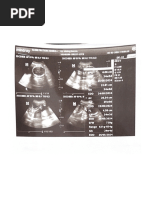

{6} BRISKesenatan ‘Surat PernyataanPelayanan di FKTP entrees (00978021 - KLINIK KEMBAR SEHAT No Kunjungan: co07B02t0T24P000z72 ae eee eee Targa tai sree NomorkKeru Peseta + 00255505904 Une 2s tau 10 buen 23 Nk teostssvoceeoo02 TongoatPelayanan 120112004 Noma urana JenisPelayoran = RTP Jers Kamin Pereneuan ‘mat USUN ESA Nomar = Pelayanan 1 Pelayanan ANC Terar pan lh nendapotinplaynen tanga shanakan Dye seta merry cl otros osha pose soba Soh Fan Karp enyaton baa Patents Kaveh uk mevggurakan ores es 9 cu nanan panomn rovan R Posen Kao Wh uriara otep yang dapat stung O9 3164 F/(TS F 212024 10:15:55 "G) BPISKesenatan ‘enteral Formulir Klaim Pelayanan Primer 00978021 - KLINIK KEMBAR SEHAT Nomot Reka Meds No Kurjungan: o0a7H02{0124P000272 Tonga! Late ‘n2008 ‘Nomor Karu Poser. 0028sSe96084 ‘uma Staton 0 ten 23h Nik ‘e0518s7025e0002 TaresoPeloyanen : 2012028 Nama MuTIARA Jing Peloyanan ITP seni Klan Perempuan lanat [DUSUN I DESA RANTAUJAYA, ‘Kolanan pasion saat dtang ke PRTP: cg PEMERIKSAAN FSIC Pomertaaan Generale Tubu Tanda Vital ots Pau: Kesadaan —:Campesmenis —sutu anc ‘dung: annua: Sete sMimmilg—Dasele 75mm : 3 few Rate :opmem —eonfide Teoma ae Tinggi Baden: 155em BertBadon 68.00% ‘iin sia: UnglarPent: 7300 em i 7220, cats . ener ‘stems hana: ‘Pemerisaan Penang Laboratorium: (7) Raditog: (7) Eloktraseriogem (7) ‘iwayat Alegh Dagnosa rime Toran Pestana screening, unspactos Moniadamentasa: piagnosa Sehunder _ ime: ‘Tindahan Prosedur) Progneea JENS TAGINAN NON KAPITAS! Peleyanan ANC: Poloyanan ANC 1 (Sam) eangan USG, Usa Keren: 9 mings “Tenags Kesehatan “r RAYHOND OS WARE iiaya yong aajoran pono ‘Kirangu hl sya bal eave dengan dae playa yong brian den dapat Syeonegunjowabhan Nomor MR Nama Umur Jenis Kelamin ‘Alamat Klinik Pratama Kembar Sehat “JL RE. Martadinata No 67 ,RTON / RW/O1 Kel. Kandang. Kampung Melayu, Kota Bengkulu, Bengkul ae211 os211274842 Resume Medis ‘R002428 Tanggal Pemeriksaan = 12 Jan 20241025 MUTIARA Dokter dr Raymond Oswart 28 tahun 11 bulan 26 har Perawat ererpuan Analis Lab GANG RAYARTO3RWOZKANDANG —_Diagnosa MAS, , Bengkulu, Catatan Dokter Subjektif : KONTROL 2 BULAN LAGI Obgyn Obstetri Trimester 1 cs Ada Intrauterine FE Ada Tunggal ys Ada FHR Ada Frekuensi 155 dpm RL. 281mm minggu NT 4.29. mm Kesimpulan _: G1POAQ HAMIL 9 MINGGU ANC 1 Obstetri Trimester 2/3 Posisi BPD mm He mm Bd gram ac _mm UK rminggu FL mm Pp . Plasenta - Ica FHR dpm Gerak Janin =~ Jenis Kelamin Kesimpulan =~ Ginekolog! Uterus pee Ukuran: =x =x= mm Ovarium Kanan :~ Ovarium Kiri =~ Massa 5 Kesimpulan ae ey Be Ee tay erry Corl EDD 14/08/2024 Pe Mae oe) Cry rr EDD_ 12/08/2024